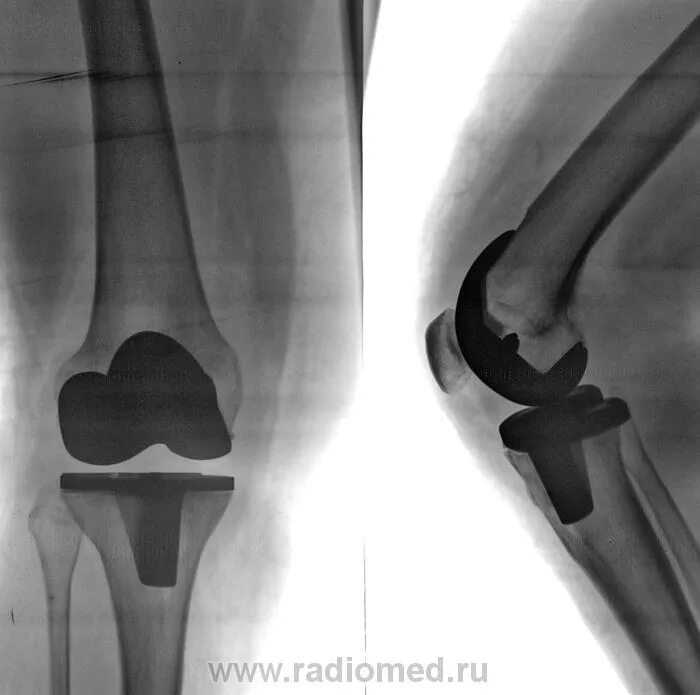

Эндопротезирование коленного сустава чебоксары